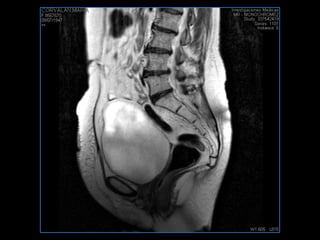

PROTOCOLO pelvis SAG T2, Y FAT SAT (FINOS) AXIAL T1  AX FAT SAT CON   GADOLINIO :  AX T1 Y COR T1 SAT: NO  FASE: RL THK: 3MM  COIL:  GAP: (FACTOR 1.4) 1MM FOV: 40 CM NEX:2 SINCRONIZACION RESPIRATORIA EN 3 O 4 CICLOS ALE